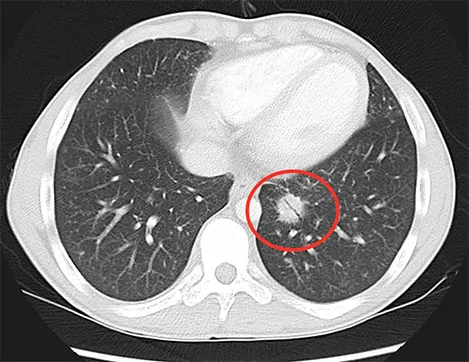

Os exames de diagnóstico por imagem são aliados na detecção dessa doença. De acordo com o médico, com esses recursos é possível localizar lesões nos pulmões do paciente e são importantes também para identificar a extensão da doença”, esclarece.

Com o avanço da tecnologia, a medicina diagnóstica é uma aliada no rastreamento dessa doença. Além da radiografia, a tomografia computadorizada do tórax é outro recurso para identificar nódulos ou massas suspeitas no pulmão, permitindo determinar o tamanho, a localização exata do tumor e a presença de metástases, quando o câncer atingiu outros órgãos.

Segundo o Dr. Augusto Romão, a tomografia computadorizada também é utilizada quando há necessidade de biópsias em áreas suspeita de câncer.